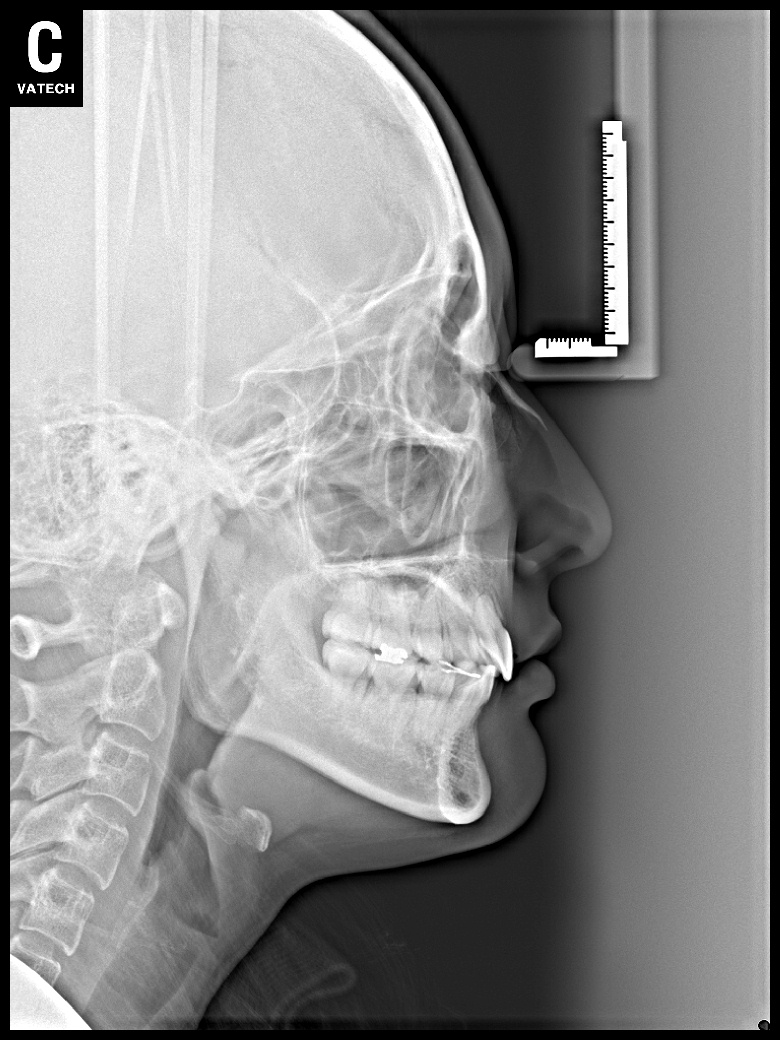

치료 전 사진입니다.